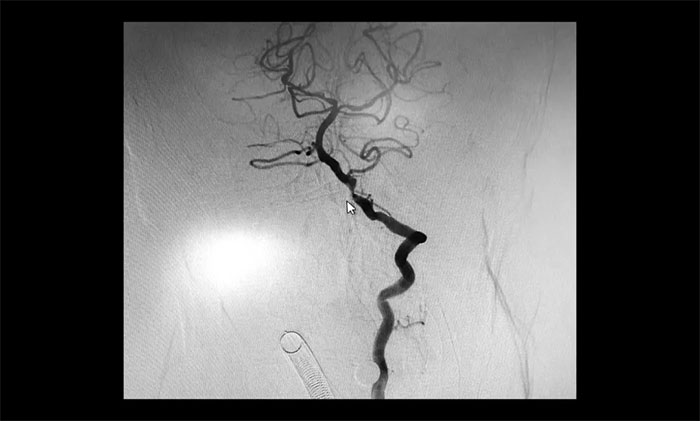

▲ 术后,左侧颈内动脉狭窄明显改善

术后康复观察一月余,于耀宇主任团队再次为曹老伯行右侧颈动脉支架置入及左侧椎动脉支架置入手术。术中造影显示,右侧颈内动脉起始段重度狭窄,狭窄长度8mm左右。左侧椎动脉 V4 段重度狭窄,长度6mm左右。运用娴熟扎实的技术,在充分做好脑保护的前提下经过多次球囊扩张后,顺利释放支架于狭窄处。造影提示支架打开良好,血管狭窄基本恢复正常,支架贴壁佳,支架内血流通畅,远端血流良好。